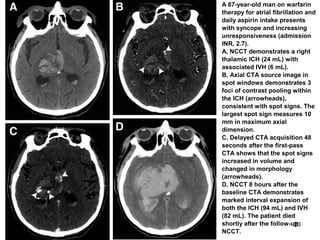

A 67-year-old man on warfarin

therapy for atrial fibrillation and

daily aspirin intake presents

with syncope and increasing

unresponsiveness (admission

INR, 2.7).

A, NCCT demonstrates a right

thalamic ICH (24 mL) with

associated IVH (6 mL).

B, Axial CTA source image in

spot windows demonstrates 3

foci of contrast pooling within

the ICH (arrowheads),

consistent with spot signs. The

largest spot sign measures 10

mm in maximum axial

dimension.

C, Delayed CTA acquisition 48

seconds after the first-pass

CTA shows that the spot signs

increased in volume and

changed in morphology

(arrowheads).

D, NCCT 8 hours after the

baseline CTA demonstrates

marked interval expansion of

both the ICH (94 mL) and IVH

(82 mL). The patient died

shortly after the follow-up

NCCT.